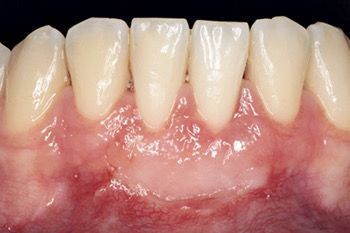

Chirurgia parodontale

Se necessari si eseguono interventi chirurgici parodontali mirati a risolvere varie problematiche che si possono riscontrare in entrambe le arcate, quando le situazioni sono di una certa gravità.